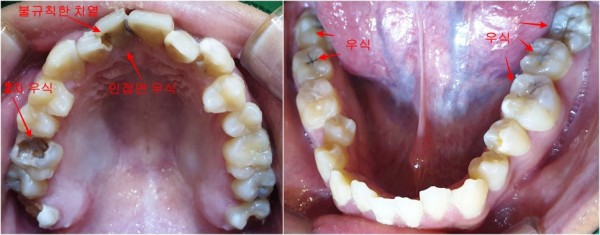

구강 검진 결과, 예상보다 상황이 심각했습니다.

오랜 기간 방치로 인해 전체적으로 충치가 상당히 진행된 상태였습니다.

특히 치열이 불규칙하게 배열되어 있어 칫솔질이 어려운 부위에

집중적으로 우식이 발생한 것으로 보였습니다.

상악 좌측 제1대구치(#16)에는 기존에 인레이 치료를 받으셨던

부위 아래쪽으로 2차 우식이 진행되어 인레이가 탈락된 상황이었고,

앞니 부분에도 상당한 우식이 관찰되었습니다.

전반적으로 여러 치아에 걸쳐 치료가 필요한 상태였죠.